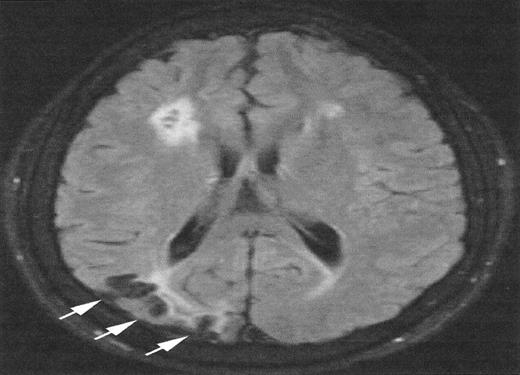

Magnetic resonance imaging (MRI) from a child with sickle cell anemia (SCA) and Moya-Moya.

The severe hemodynamic compromise associated with the Moya-Moya vasculopathy is associated with overt stroke secondary to a right parietal cortical infarction (white arrows). The signal hyperintensities in the frontal regions correspond to silent cerebral infarctions.

The relationship between SCI and other patterns of brain injury that can be seen in children with SCA is not well defined. In part, this is because SCI can only be identified with surveillance MRI evaluations, which have only recently become routine in some clinical centers. A common finding is cerebral atrophy. This is a non-specific finding that serves as a marker for disease severity in the brain. Another common finding is Moya-Moya, a description that comes from the Japanese for “puff of smoke” because of the angiographic appearance of secondary extensive collateral formation. Figure 2 is a time-of-flight MRI angiogram in a child with SCA and Moya-Moya. The arrows indicate the stenosis/occlusion of the distal internal carotid arteries. The child with SCA and Moya-Moya shown in Figure 3 has an extensive area of cortical infarction corresponding to the distribution of the posterior cerebral artery (arrows) and silent cerebral infarct in the frontal regions.